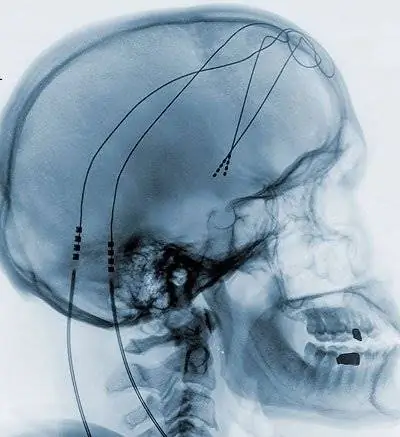

Во время глубокой стимуляции мозга врачи используют электрический кардиостимулятор мозга, чтобы воздействовать на функцию определенных областей мозга. В текущем исследовании они имплантировали электроды в так называемое прилежащее ядро. Это важная часть так называемой «системы вознаграждения». Это гарантирует, что мы помним хороший опыт и погружаем нас в состояние предвкушения. Без системы вознаграждения мы бы не строили планов на будущее, потому что не смогли бы пользоваться плодами этих планов. Бездеятельность и неспособность получать удовольствие - два важных признака депрессии.

Но что именно делает раздражение прилежащего ядра? «Мы смогли использовать сканер мозга, чтобы показать, что метаболическая активность различных центров мозга изменяется в результате стимуляции», - говорит Шлепфер. «Очень важно: метаболические изменения затрагивают не только само прилежащее ядро, но и другие области так называемой лимбической системы. Именно здесь мозг обрабатывает эмоции».